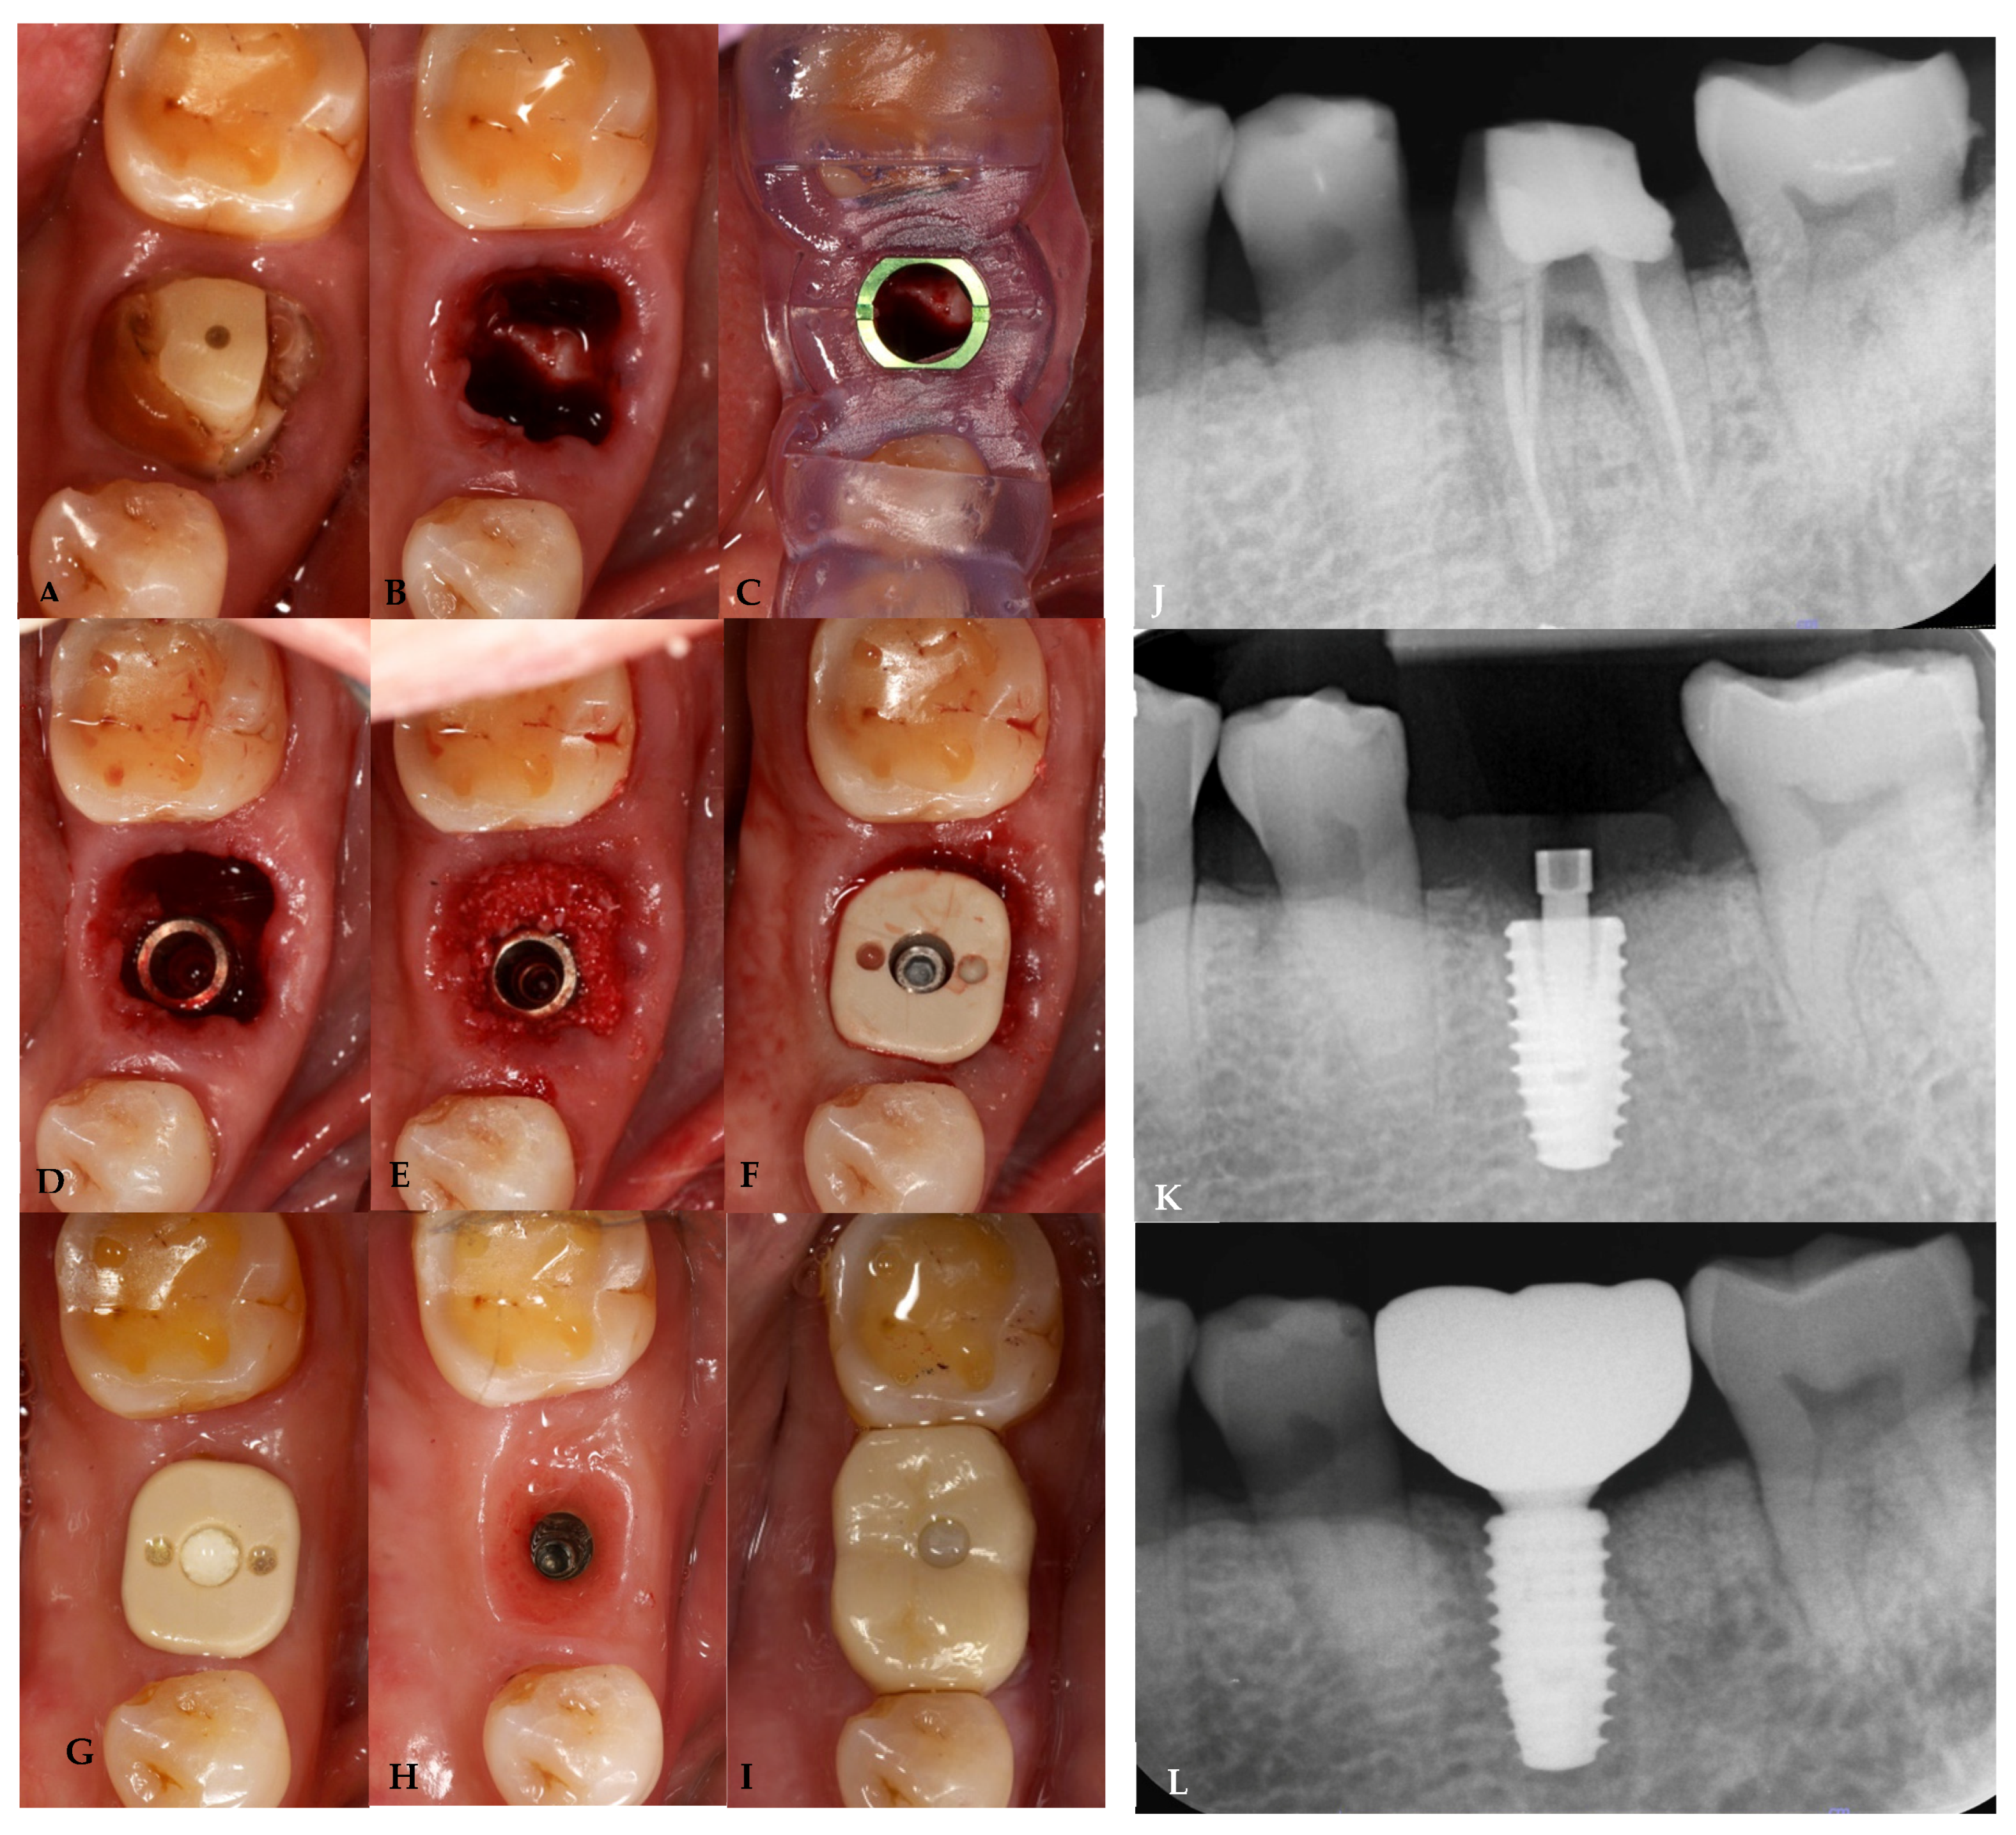

2.7. Case Presentation

3.2. Hard Tissue Parameters

Marginal Bone Change (mm); mBC and dBC